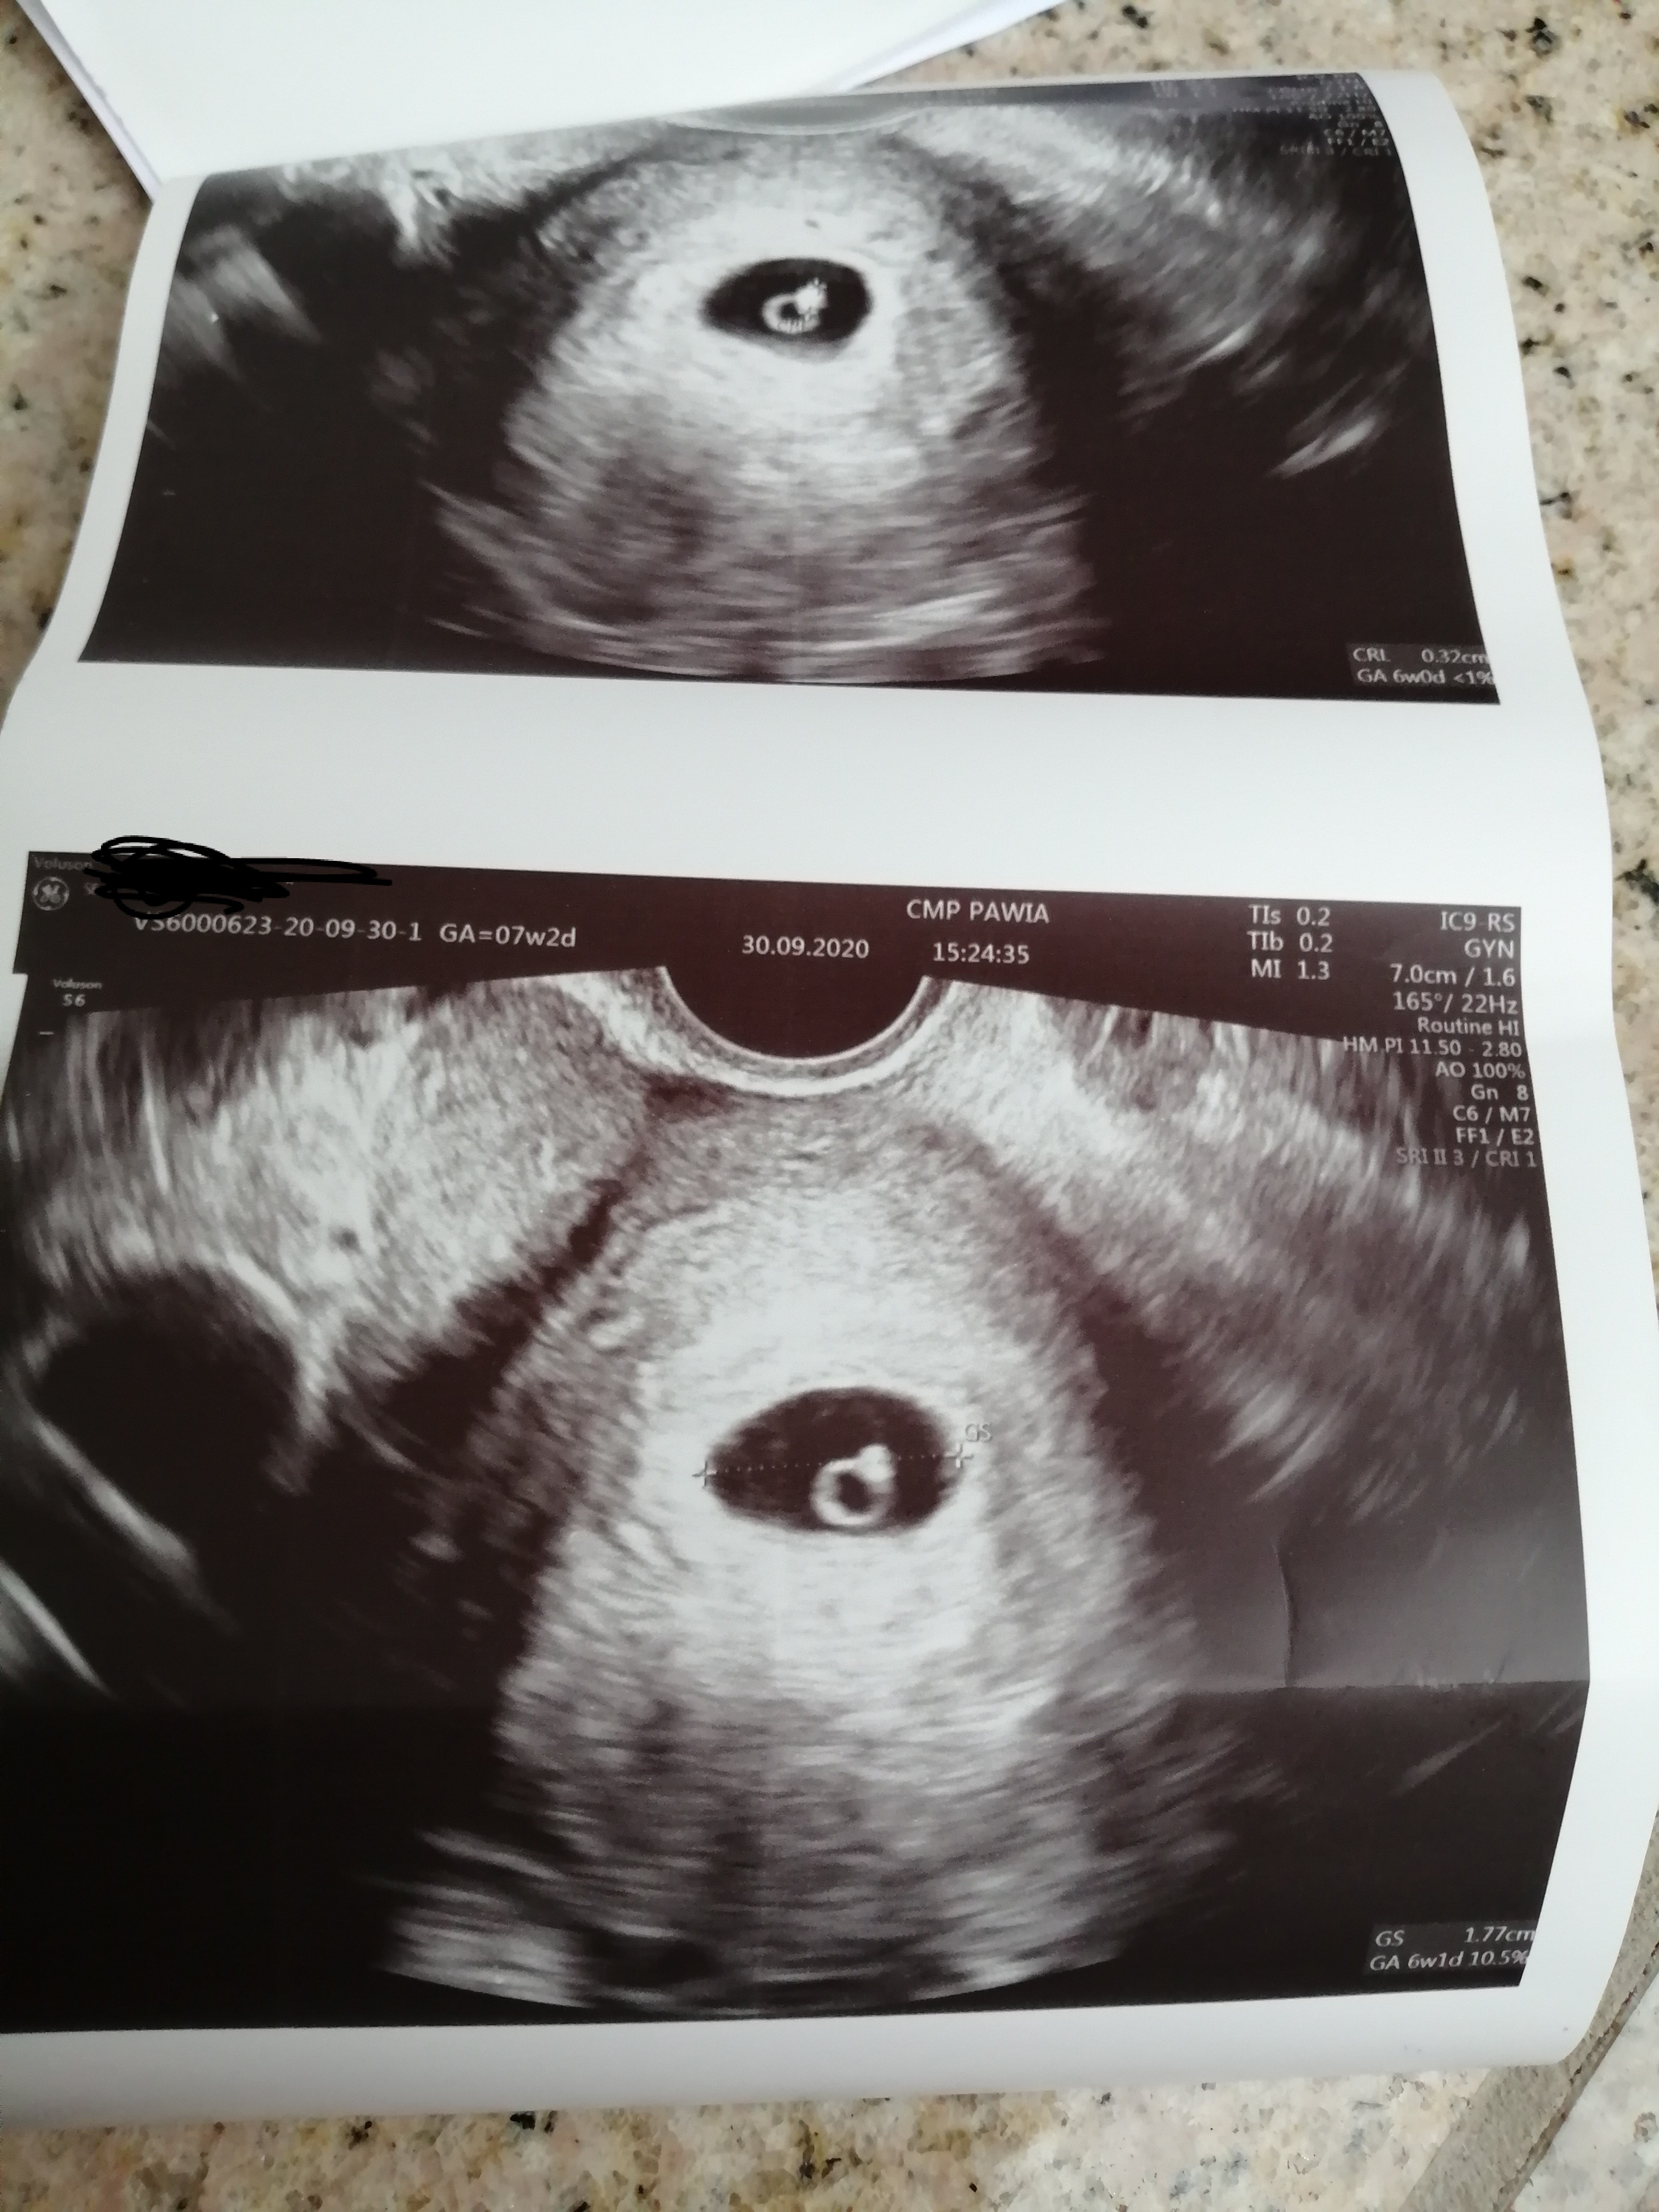

A więc sytuacja wygląda tak. Ogolnie jak na razie jest ok, wyszło że jestem w 6 tygodniu, serduszko bije 160/min nie słyszałam więc nie wiem czy tak poprostu wpisała. Ale dała marne szanse na utrzymanie. Mnóstwo leków i mam się oszczędzać. Może się uda. Tak mi powiedział lekarz.. Nie owijał w bawełnę

Na zdjęciu mój mały skarb naprawdę przypomina mi mały pierścionek. Popłakałam się jak wyszłam od lekarza.

Załączniki

• IMG_20200930_160516.jpg

IMG_20200930_160516.jpg

1,7 MB · Wyświetleń: 102